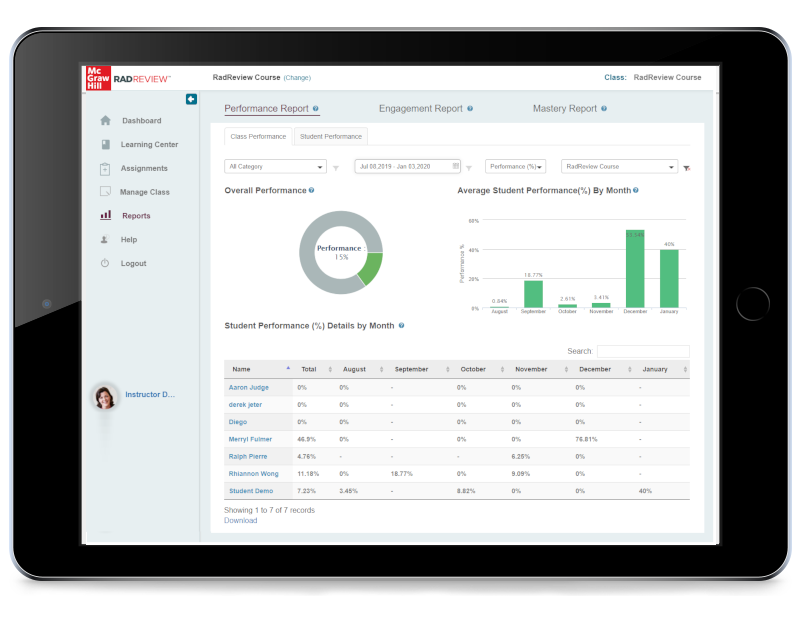

Rad Tech Exam Instant Results Test Portal, The healthcare education landscape is rapidly evolving, and technology now plays a major role in how exams are conducted and evaluated. One of the most helpful advancements for radiologic technology students is the …

Rad Tech Exam Score PredictionTests, Preparing for the radiologic technologist (rad tech) exam can be stressful, especially when you are unsure how ready you really are. Many students study hard but still feel anxious about their final results. This is …

Rad Tech Exam Subscription Test Platform, Preparing for a radiologic technology certification exam can be challenging, especially with the wide range of topics and the pressure to perform well on test day. A rad tech exam subscription test platform offers …